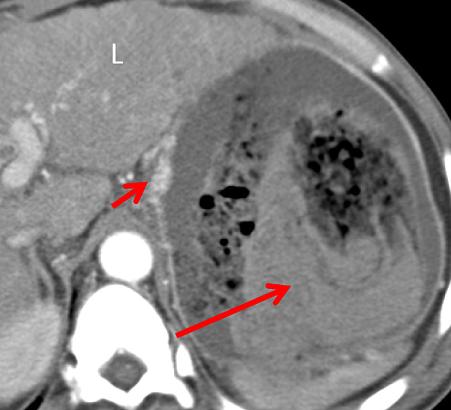

气肿性胃炎是一种罕见的发生于胃部的致命性疾病,临床上以胃壁内出现游离气体为主要特征。 病因包括感染、缺血、药物及特发性等,常见的病原菌包括链球菌、大肠杆菌、金葡菌等。 易感因素包括免疫力低下(如糖尿病及恶性肿瘤患者)、既往有胃黏膜损伤病史(如酗酒、服用 NSAIDs)等。 患者多以急性腹痛、发热、恶心甚至消化道出血为主要表现。

CT 表现为:胃壁增厚及粘膜下水肿,胃壁内积气,这些气体可进入门脉系统致门脉系统积气。

中年男性,突发恶心、呕吐。CT 增强门脉期示胃体部胃壁稍增厚,增厚的胃壁内可见散在气体,另外肠系膜静脉积气。

老年男性,气肿性胃炎,上腹部疼痛。CT 平扫示胃壁积气,腹腔及门静脉积气。